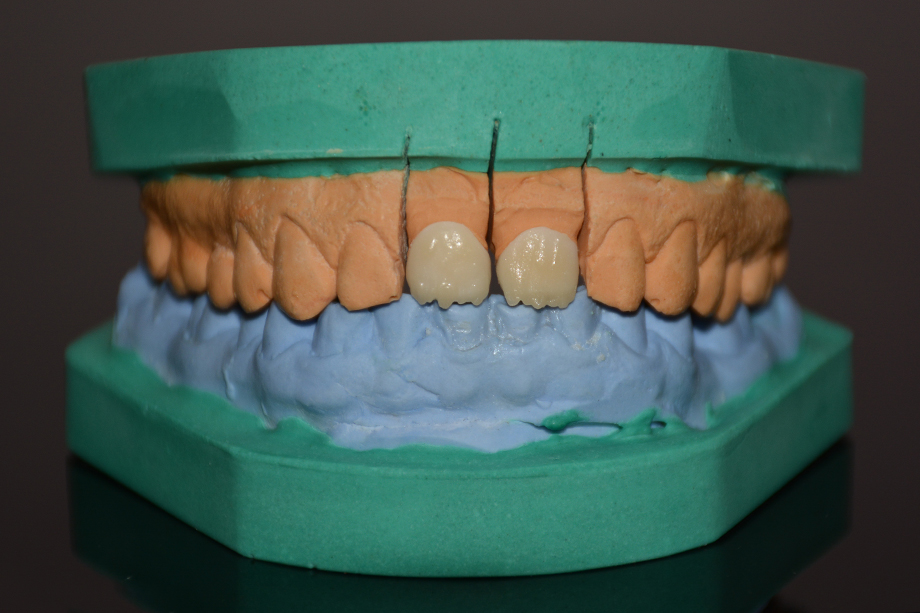

Patientenfall: Restauration zweier Inzisiven mit Zirkoniumdioxid in Kombination mit VITAVM®9

VITA VM 9 ist eine natürliche Feldspat-Verblendkeramik mit Feinstruktur für Zirkondioxidgerüste, VITABLOCS Mark II und PM 9.